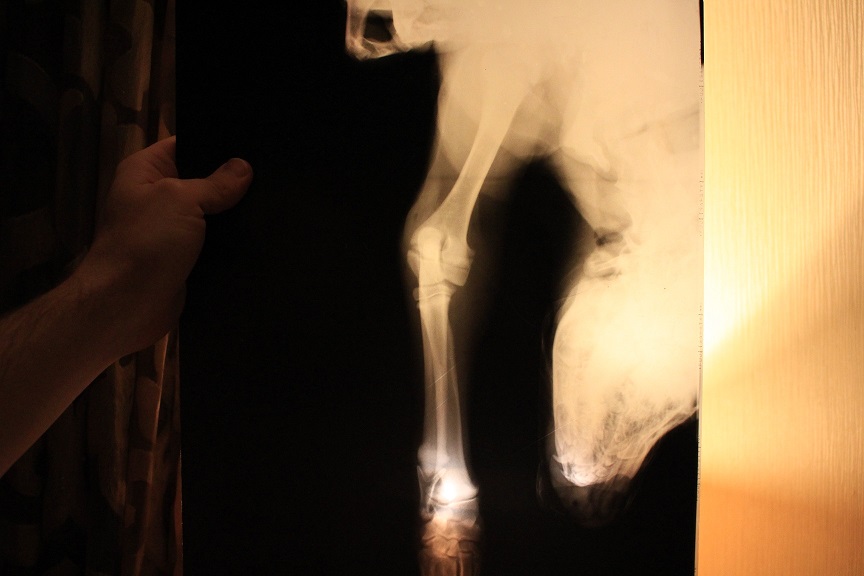

доброго. у нас прокус в месте роста локтевого сустава. локоть работает, а вот запястье на этой лапе болтается (как тряпочка) подскажите, это из-за травмы, или что-то вражденное. до прокуса, все было хорошо

Если до травмы все было нормально - точно не врожденное.

Надо к врачу, проверять чувствительность. Может быть травма нерва, связочного аппарата. Щупать надо.

ходим каждую неделю на контрольный снимок и на консультацию. после травмы прошло 3 недели. чувствительность по всей лапе есть.

А зачем каждую неделю снимок?dvornachka писал(а):ходим каждую неделю на контрольный снимок и на консультацию. после травмы прошло 3 недели. чувствительность по всей лапе есть.

Видио как ходит. Что говорит лечащий врач?

врач говорит - нужно время. ждите, попробуйте найти где поплавать.

по неровной или мягкой поверхности она ходит не хромая, опирается на лапу.

только на ровной хромает. на улице бегает, держит этой лапой палочки, может дома просить вкусняшку этой лапой.

это улучшения через неделю после травмы. но меня беспокоит именно мягкость в этом месте. болтается она как сосиска...

Когда запястье болтается, то животное его не контролирует и ставит лапу как бог на душу положит. Обычно на то самое запястье.

На снимках запястье не совсем корректно. Изменений в костной ткани не видно. Да и не наступала бы она.

так она ни когда не наступала. сразу после травмы, просто ее на весу держала. потом только при команде сидеть могла поставить на запястье. когда лежала или в расслабленном состоянии лапа часто была согнута во внутрь. я подходила и расправляла. фиксировать нам не рекомендовали.zver писал(а):Когда запястье болтается, то животное его не контролирует и ставит лапу как бог на душу положит. Обычно на то самое запястье.